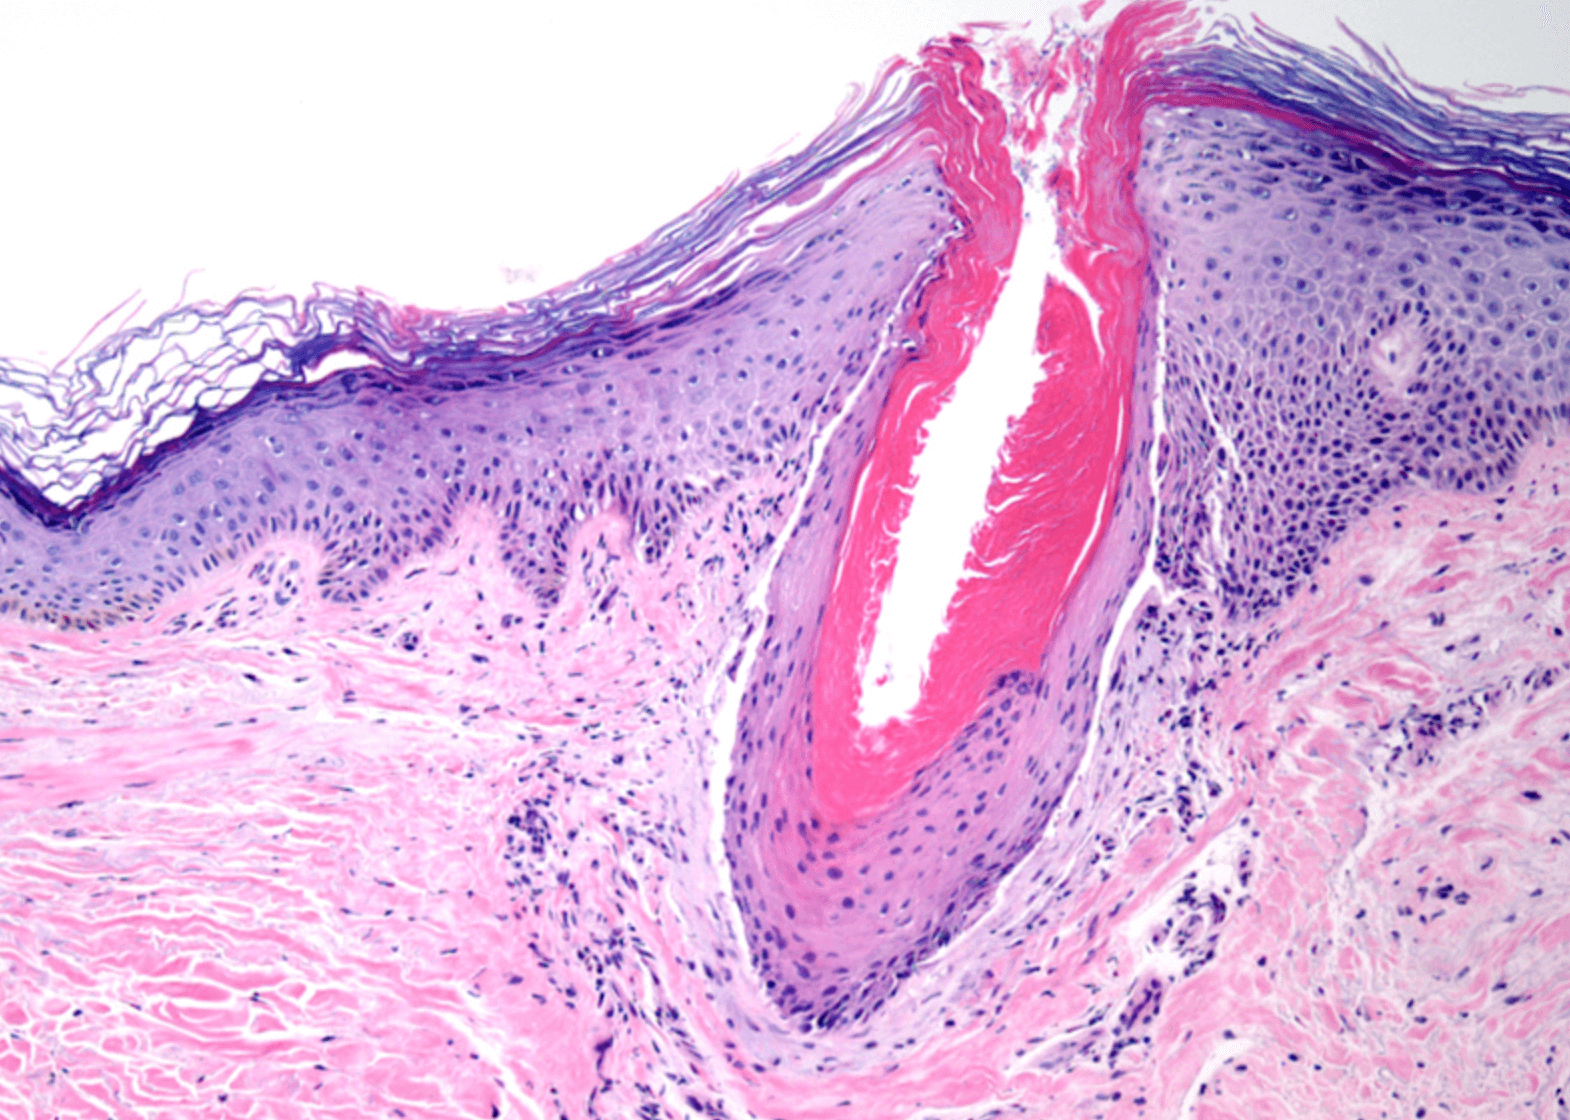

모공각화증

닭살돋은 느낌의 붉은 피부를 모공각화증 이라고 생각하시면 이해도가 쉬울것 같습니다. 이러한 작은 융기는 모낭을 막아 죽은 세포 이며, 보통 붉읂색 또는 갈색으로 나타납니다.

모공각화증은 유해 물질과 감염으로부터 피부를 보호하는 단단한 단백질인 케라틴이 축척되어 발생하며, 케라틴은 모낭의 열림을 막아 거칠고 오돌토돌한 피부를 만듭니다.

각화증 필라라스는 모든 다양한 연령대에서 발생할수 있지만 어린아이들에게서 더 흔하게 발생합니다. 외관은 닭살과 같은 오돌토돌한 느낌을 주고, 모낭이 존재하는 피부의 어느곳에서든 나타날수 있습니다.